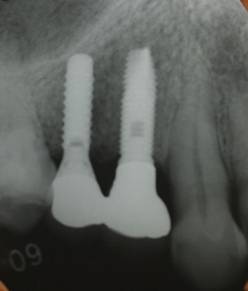

歯周病で抜歯せざるを得ず、インプラントを希望されたケース(使用インプラントはスプライン)

治療後。歯周病で失われた骨が回復しています。使用インプラントはスプラインツイストです。

インプラント装着後6年。順調に経過しています。12か月毎のメインテナンスをしています。